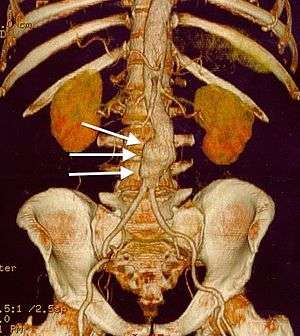

|

CT reconstruction image of an abdominal aortic aneurysm (white arrows) | |

Abdominal aortic aneurysms (3.4 cm)

-